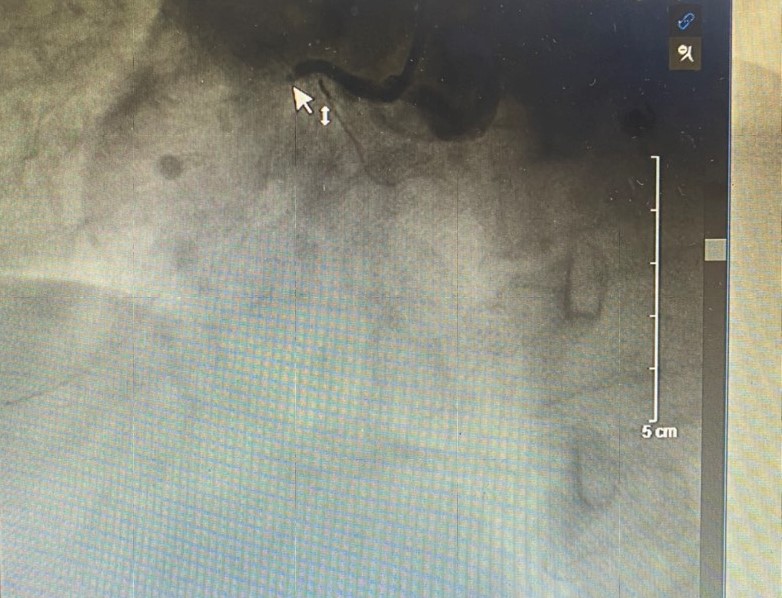

Kết quả chụp mạch vành phát hiện tổn thương nặng 3 thân mạch vành: Tắc hoàn toàn mạch vành phải, hẹp khít liên thất trước và hẹp 80-90% động mạch mũ trên bệnh nhân. Nhận định tổn thương do động mạch vành phải bị tắc hoàn toàn, kíp can thiệp Khoa Tim mạch – Đột quỵ đã nhanh chóng tiến hành tái thông mạch vành phải. Ngay sau khi can thiệp thành công, ghi nhận dòng chảy tốt, bệnh nhân đã ổn định, hết đau ngực. Nhờ được phát hiện can thiệp cấp cứu kịp thời, sử dụng kĩ thuật tiên tiến, đặt stent động mạch vành đã cứu sống bệnh nhân.

- Hình ảnh sau can thiệp